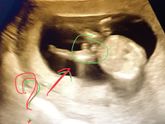

УЗИ и пол ребёнка ?27 ноября 2017 16:03 Девочки, кому на первом скрининге сказали пол ребёнка и ошиблись?